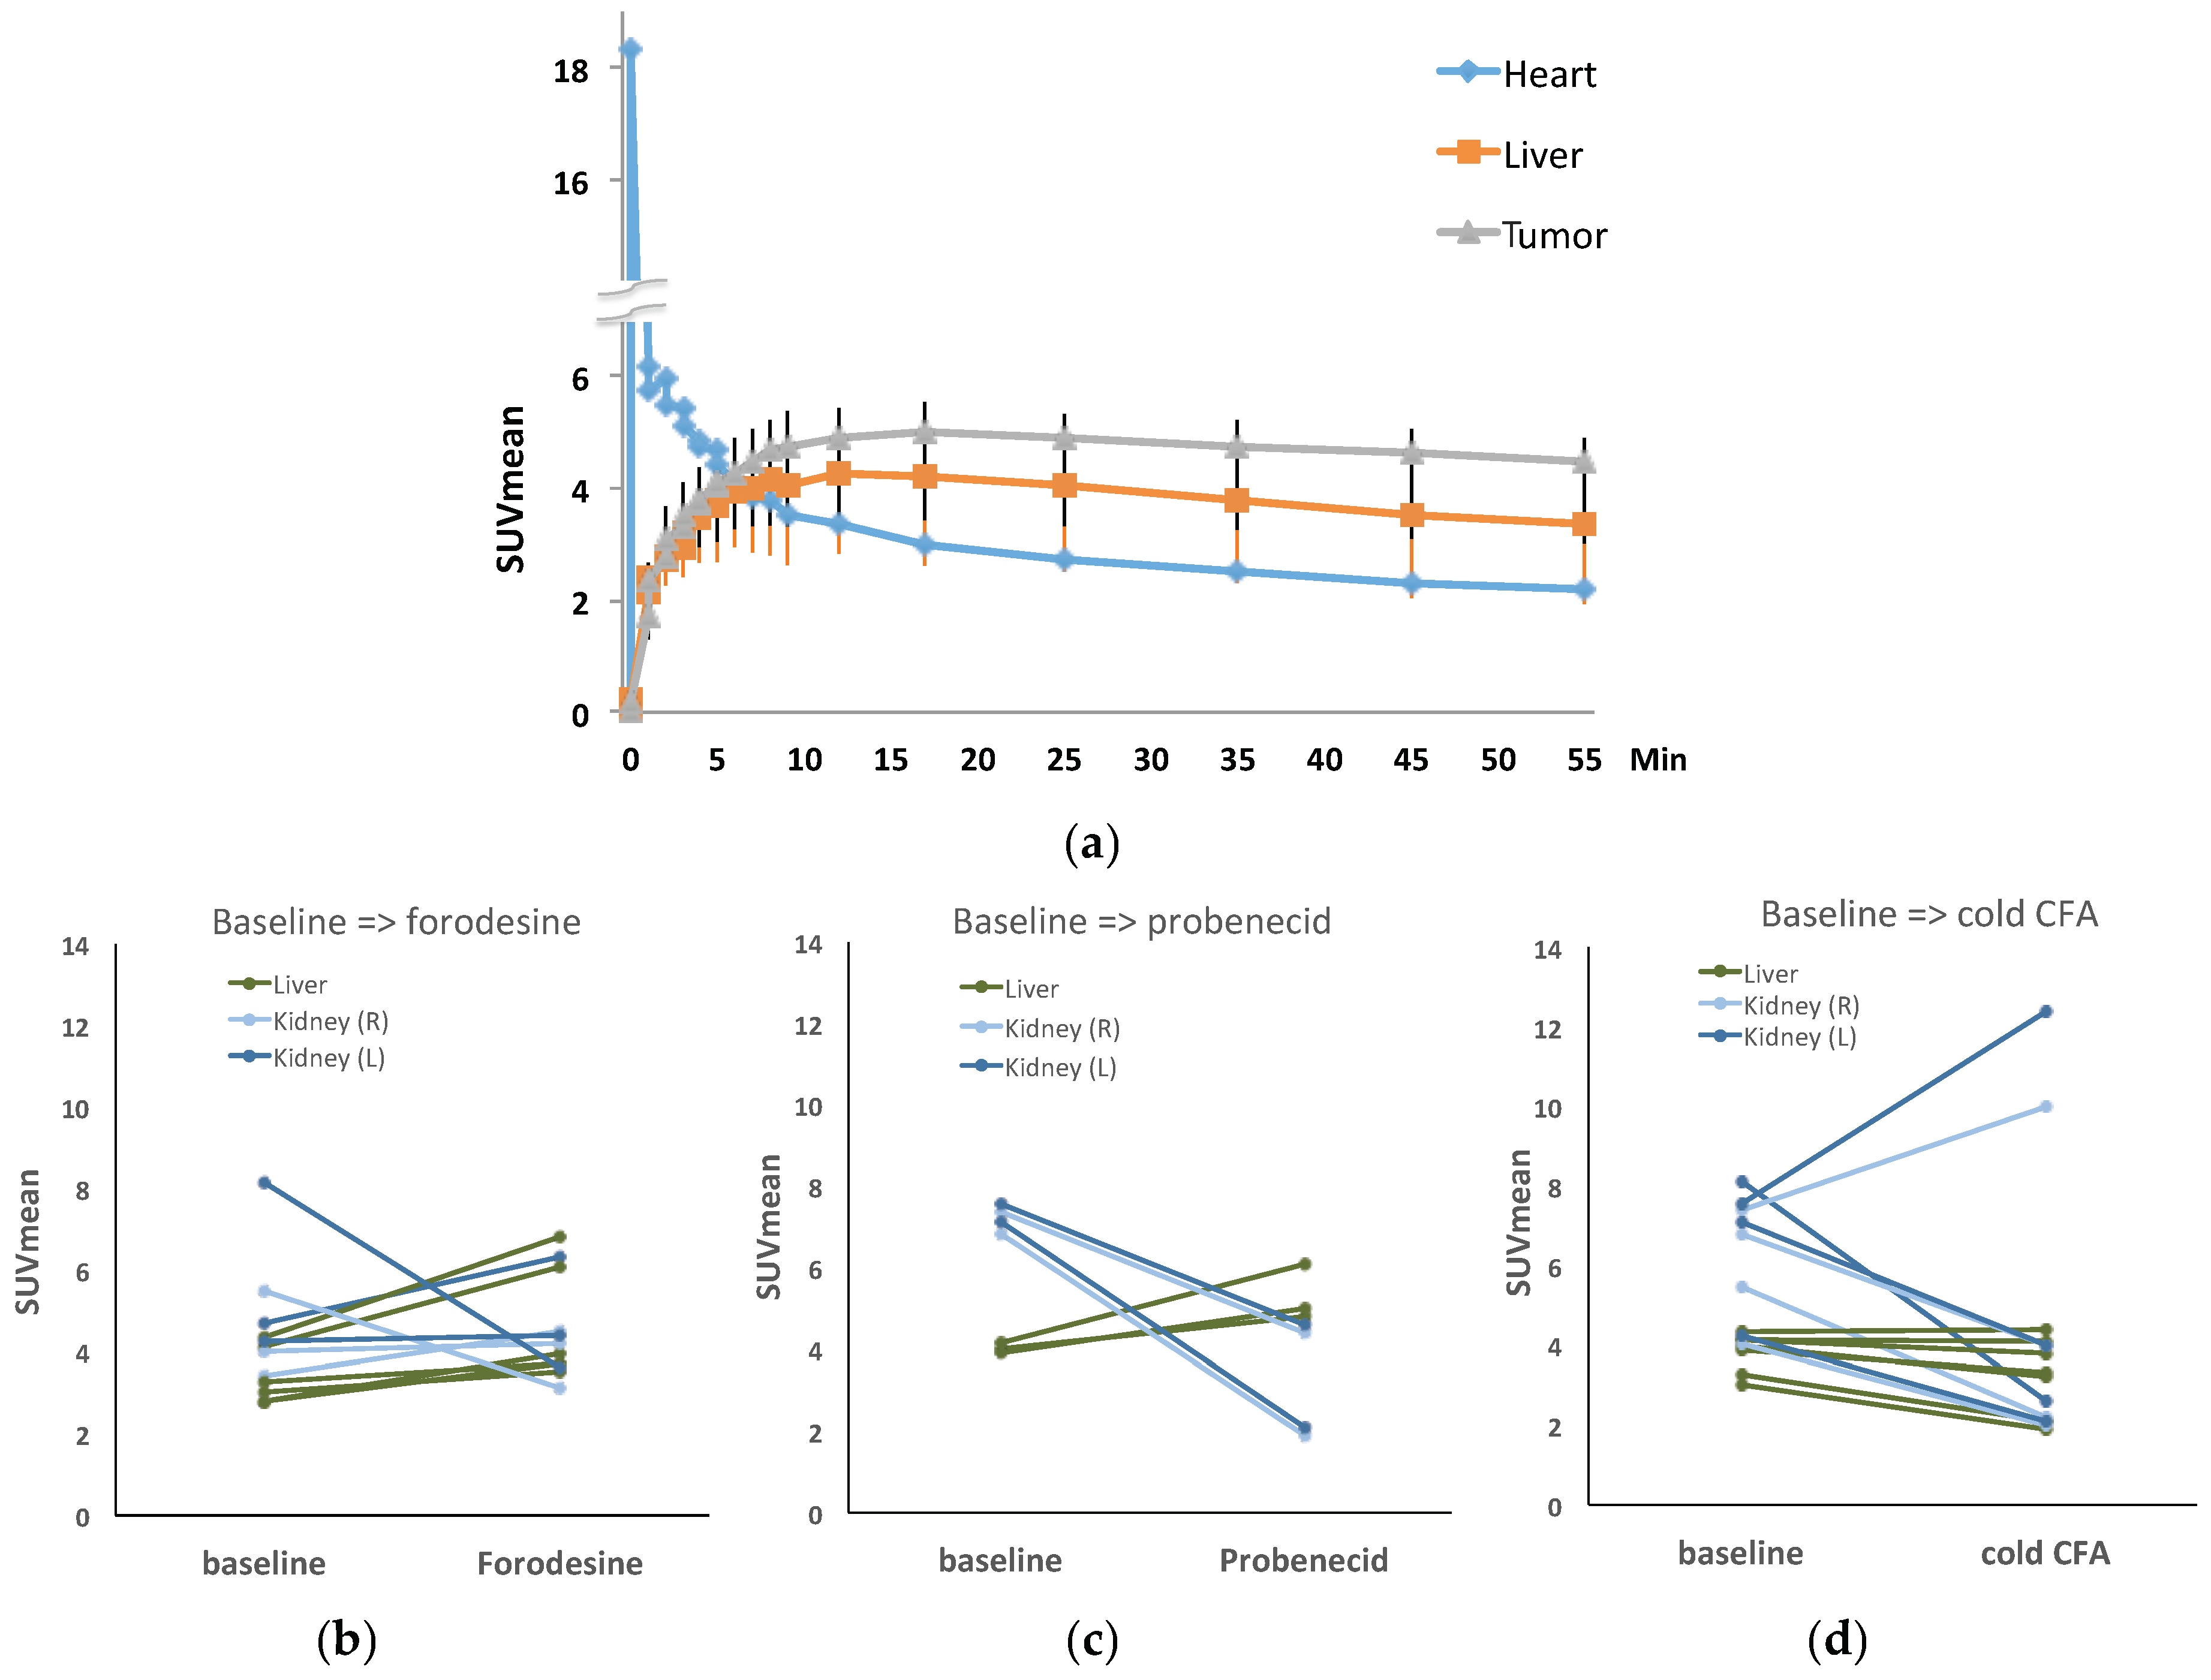

2. Results

2.2. PET Imaging